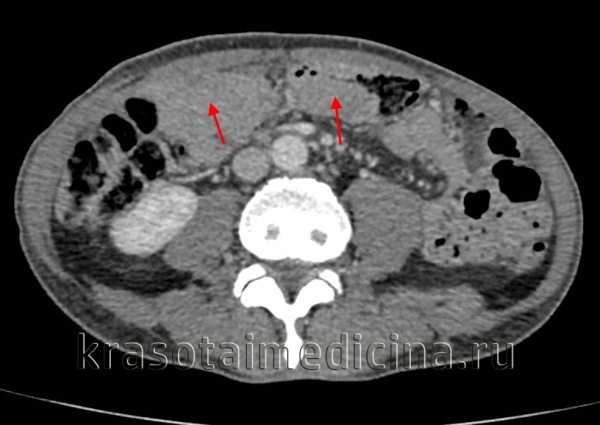

КТ ОБП/ЗП. Циркулярная мягкотканная опухоль (красная стрелка) стенки поперечной ободочной кишки, значительно суживающая ее просвет.